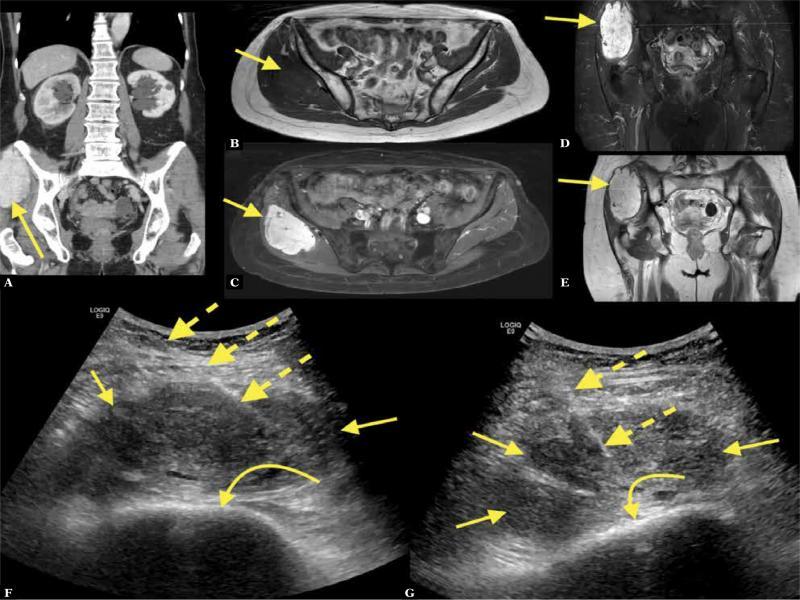

Fig. 7.

A 70-year-old patient with a history of malignant melanoma operated 3 years before presented with pain in the abdomen and right buttock. CT with intravenous contrast in the portal venous phase showed an intramuscular contrast-enhancing mass on the right ( A ; straight arrow – mass). MRI of the pelvis with intravenous contrast showed a solid contrast-enhancing tumor in the gluteal muscles ( B–E ). MRI and CT were unspecific, with a wide spectrum of differential diagnoses. The patient was referred for US-CNB ( F, G ; dashed arrows – biopsy needle, curved arrow – iliac bone). The histopathological diagnosis was extrapleural solitary fibrous tumor